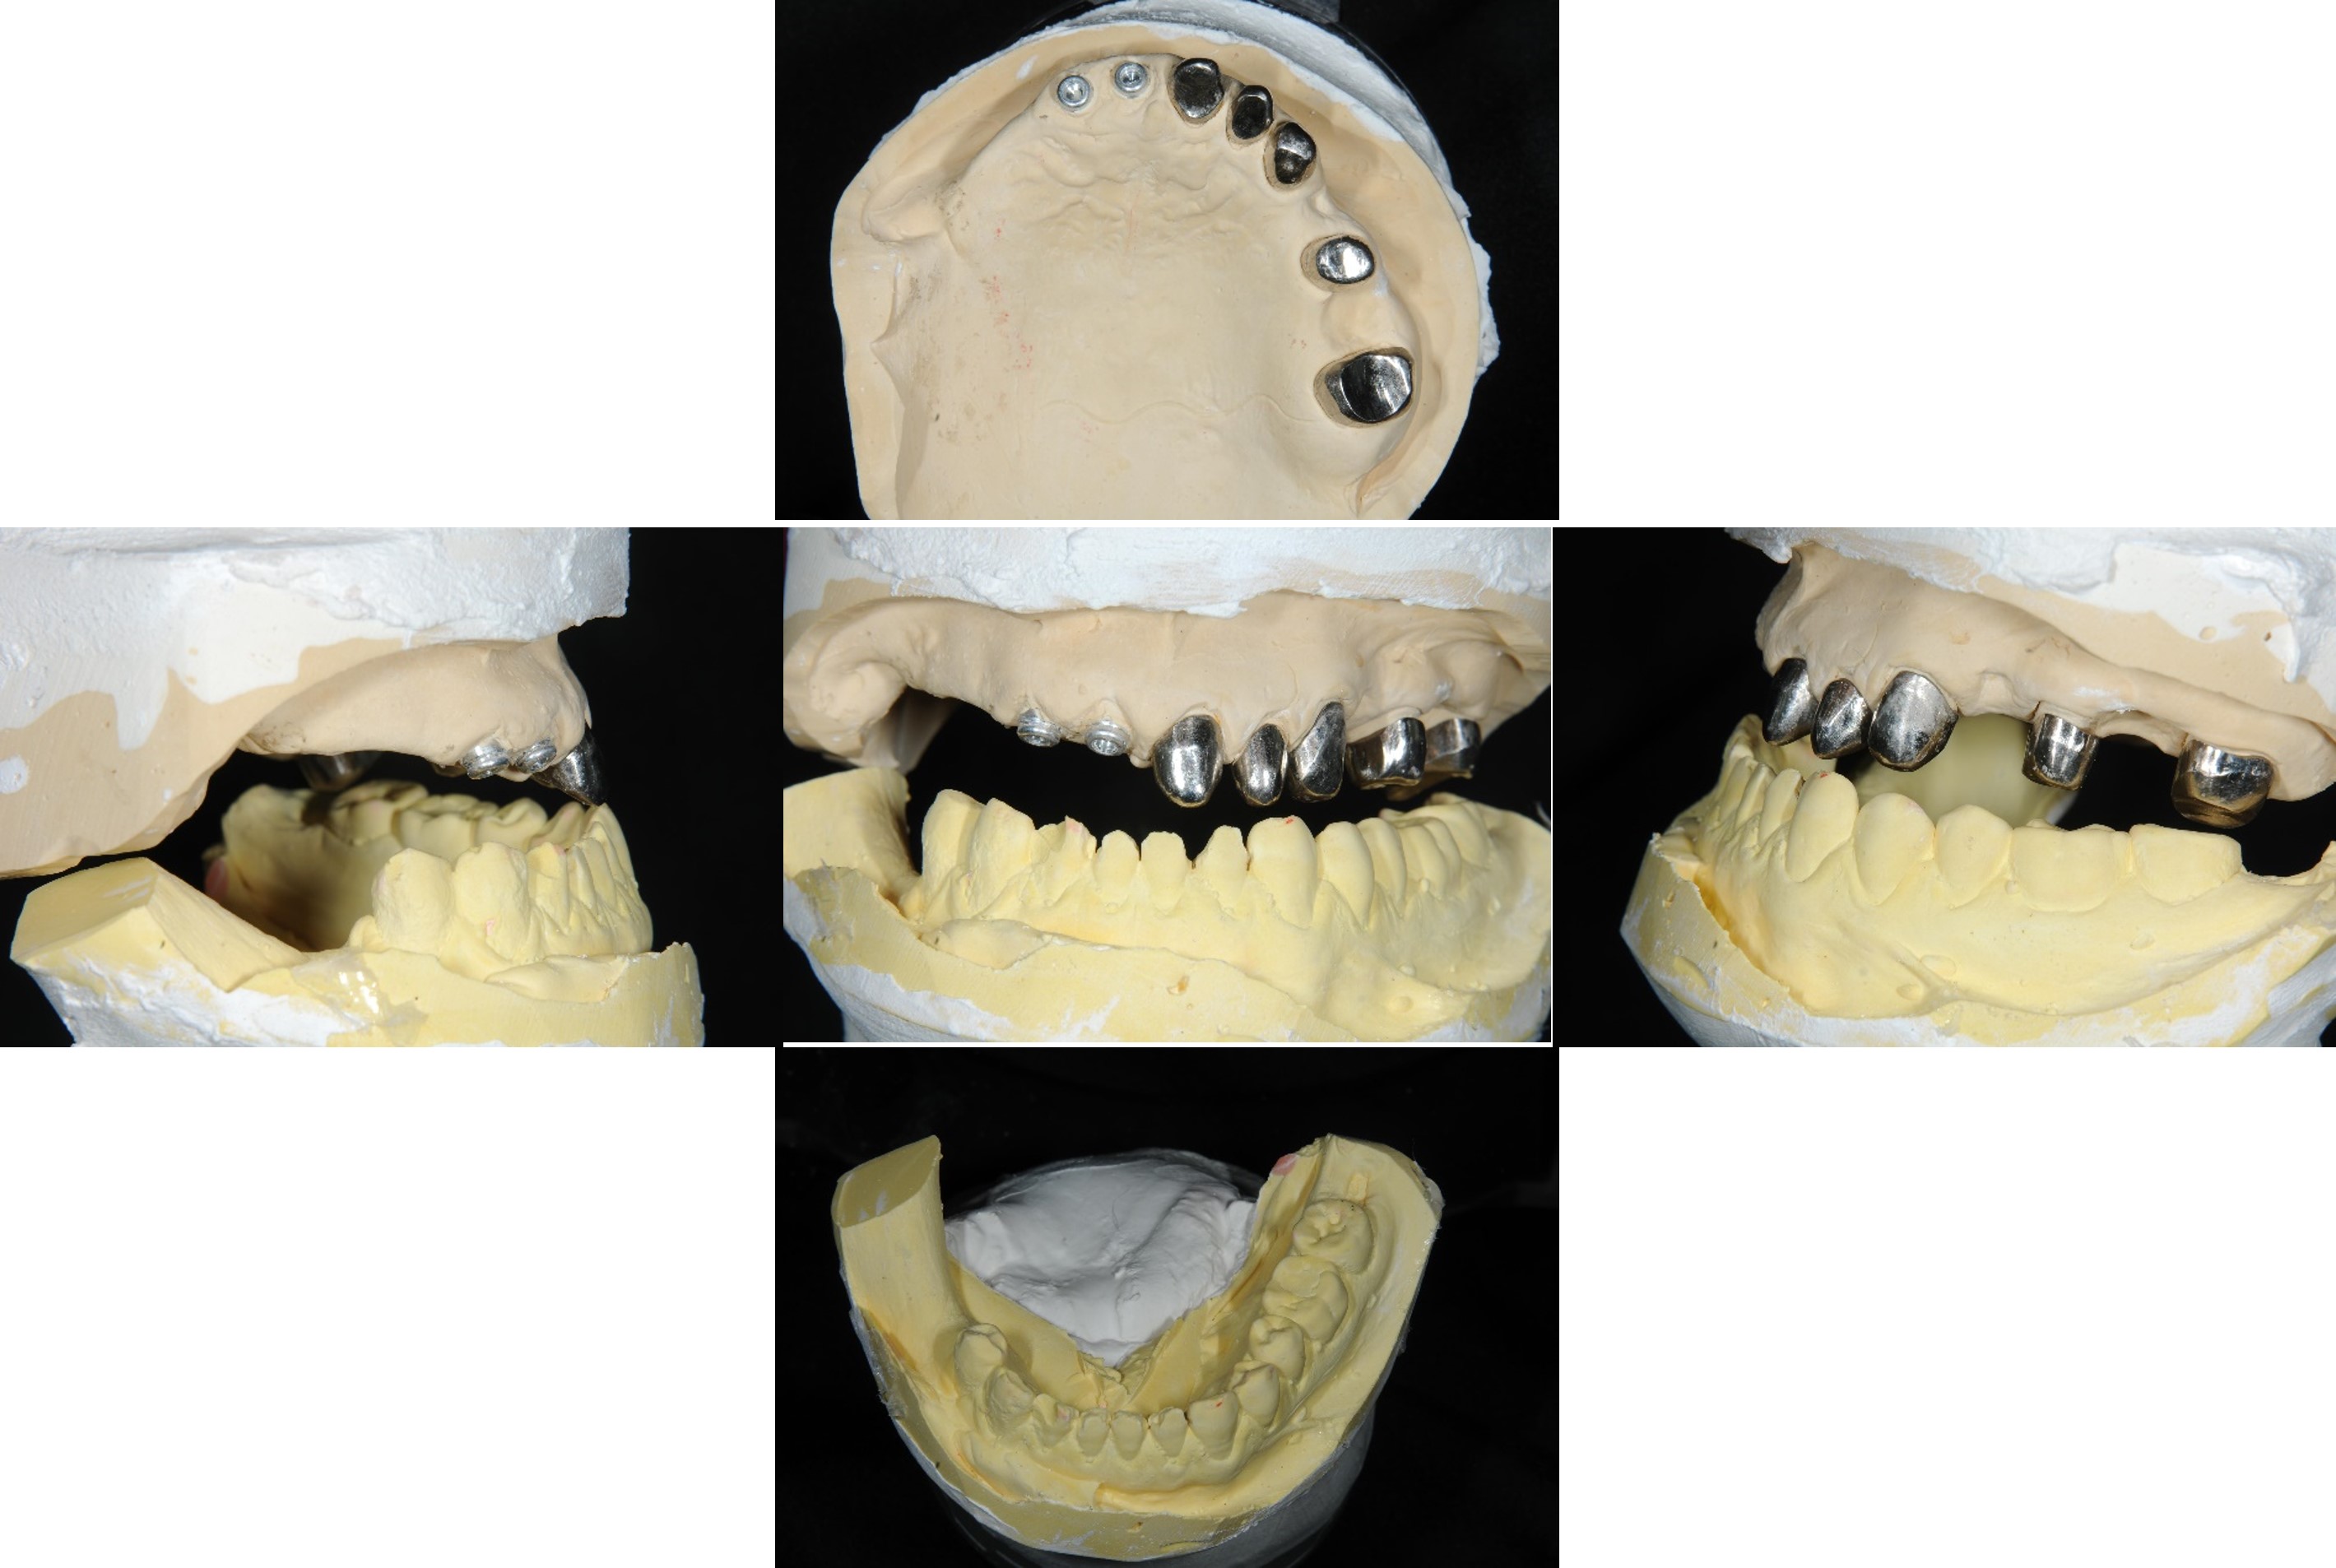

蠟型模擬最終可能成果

蠟牙製作